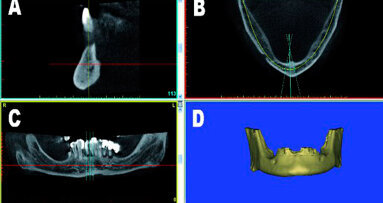

Nell’area edentula mandibolare, erano visibili un deficit osseo orizzontale e verticale che necessitava di una rigenerazione ossea ma che avrebbe permesso l’inserimento contestuale di impianti endossei (Figg. 1a-1c). La paziente, dopo valutazione delle alternative terapeutiche, sceglieva di eseguire una rigenerazione ossea protetta con l’utilizzo di una griglia in titanio customizzata contestualmente all’inserimento implantare. In una seduta successiva, venivano quindi rilevate delle impronte e veniva costruita una ceratura diagnostica con denti di dimensioni e posizione ideale per ottenere corretti rapporti intra- e inter-arcata e, successivamente, una dima diagnostico-radiologica con reperi radio-opachi, utilizzata per l’esecuzione di una CBCT.

Figg. 1a-1c_Foto clinica e sezioni di CBCT iniziali in cui si evidenzia edentulia distale all’elemento 4.5 con atrofia tridimensionale.